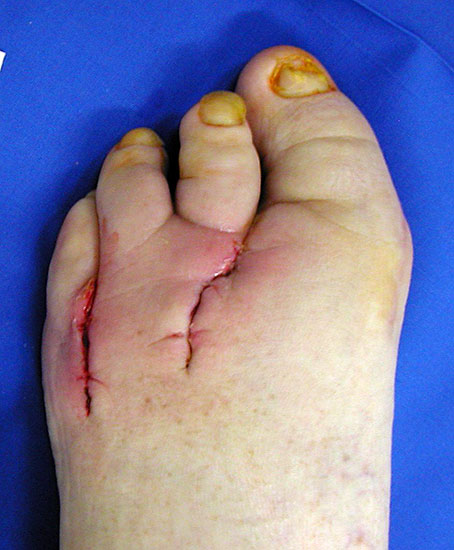

Technik

Die Zehe wird tennisschlägerartig umschnitten (Abb. 24). Falls ein infiziertes plantares Ulkus vorliegt, kann die Exzision dieses mit einbeziehen. Dies ist jedoch meistens nicht erforderlich. Das proximale Inzisionsende reicht bis an das TMT Gelenk. Das Metatarsale wird möglichst proximal osteotomiert, wobei am 1. Strahl eine Kantenbildung nach medial und 5. Strahl eine nach lateral vermieden werden muss. Es soll erreicht werden, dass die Nachbarzehen sich annähern, um das Kippen einzelner Zehen zu vermeiden (Abb. 25). Es wurde vorgeschlagen, die Fußverschmälerung durch einen Minifixateur, der zwischen 1. und 5. Mittelfußknochen angelegt wird, zu begünstigen (Bevilaqua 2013). In unserem Patientengut hat sich hierfür nie die Notwendigkeit ergeben, da sich die Mittelfußköpfe durch Narbenzug spontan annäherten und narbig stabil verheilten (Abb. 26). Bereits nach wenigen Wochen hat sich der Fuß verschmälert und bietet ein kosmetisch günstiges Ergebnis (Abb. 27).